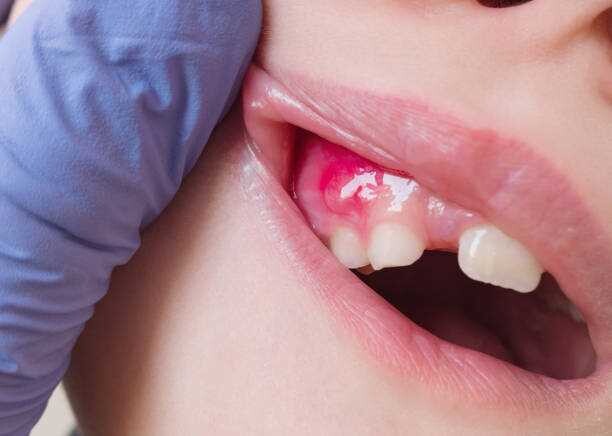

A tooth abscess is a bacterial infection found in the inner part of the tooth where pus has collected and can cause moderate to severe pain in people who suffer from the condition. Tooth abscesses can occur when a cavity has gone untreated for too long or when a crack or chip in the tooth allows bacteria to find its way into the dental pulp (the inner, soft part of the tooth) area of the tooth and gets infected.

Once the bacteria has made its way inside, it will spread down to the root and cause both inflammation and swelling. Once inflammation occurs, it will force the pus into a tight space (known as the abscess) at the tip of the root where the swelling exists.

Symptoms

Signs and symptoms of a tooth abscess include:

Persistent, throbbing or severe toothache

Extreme temperature sensitivity

Pain when performing normal chewing or biting

Fever

Swelling in the face or the cheeks

Lymph nodes under the jaw or in the neck become tender or swollen

A rush of foul-tasting fluid in the mouth followed by cessation of pain, which means the abscess has ruptured

If you experience any of the signs or symptoms listed above, you should see your dentist immediately, especially if you begin to experience swelling in your face or begin to feel feverish. If your dentist cannot see you immediately, you should go to an emergency room as it’s possible these symptoms indicate the infection is possibly spreading into your jaw and the surrounding tissue.

The only way to rid yourself of both the pain and the condition is to get proper dental treatment. You may feel a lessening of pain if the abscess ruptures, but you’ll still need to get a professional’s help. The infection could spread to other parts of your jaw and beyond to parts of your head and neck and, in a worst-case scenario, lead to sepsis, which is an infection throughout the entire body that can put your life at risk.

Tooth Abscess Treatments

Treating a tooth abscess involves draining the abscess and ridding the area of the infection. The tooth itself may be saved with a root canal treatment, but in some instances, it may need to be removed completely. Leaving a tooth abscess untreated can lead to serious, even life-threatening, complications. Your dentist or oral surgeon may recommend the following:

Root Canal Procedure — If possible, your dentist will try to save your tooth by performing a root canal. The tooth is cleaned and disinfected on the outside, drilled into and cleaned out from the inside and then filled with a safe adhesive cement to restore structural integrity (and protect the tooth from future infection). If taken care of, this restored tooth will last your entire lifetime.

Extract or Pull the Affected Tooth — Extracting the tooth is a last resort, but if the tooth cannot be saved, your dentist will elect to choose this option to preserve the health of the rest of your mouth. Once extracted, the abscess will be fully drained and cleaned to prevent further infection.

Antibiotics — If the infection is localized around the abscessed area, you may not need antibiotics. However, if the infection has spread beyond it, your dentist will prescribe antibiotics to help slow or diminish the infection, especially if you have a weakened immune system.

While the area is healing, your dentist may recommend that you regularly rinse your mouth with warm salt water and take over-the-counter pain relievers as needed to help ease any discomfort you may encounter.